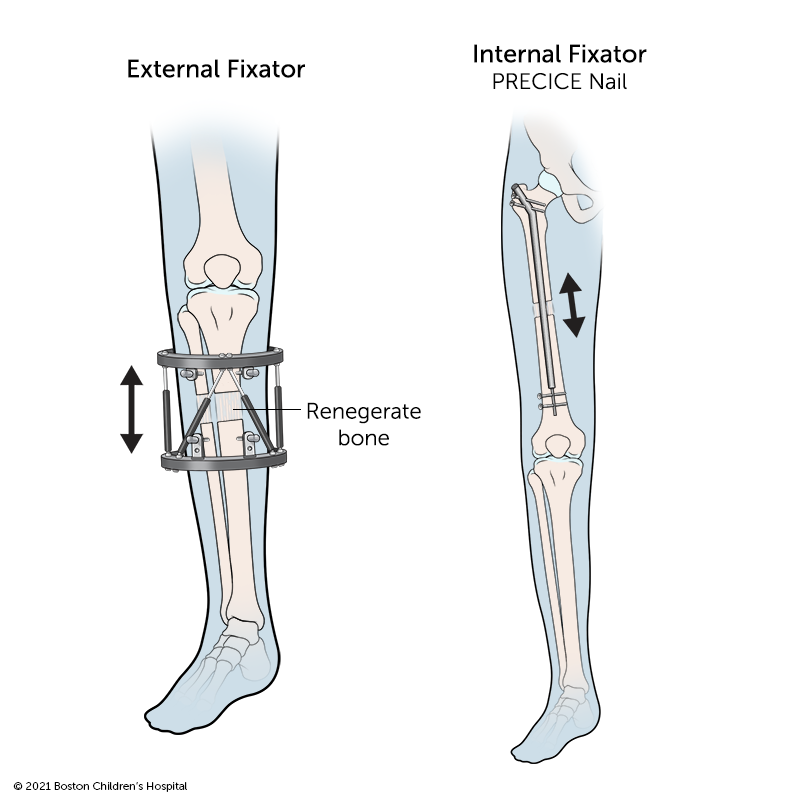

There are two types of limb-lengthening devices. One type is worn on the outside of the arm or leg. The other is an internal device that is more precise and reduces the risk of complications and infection.

External fixators are worn on the outside of the limb and are attached to the bone by pins. The patient or family adjusts the device daily to increase the distance between the two ends of bone. Once the correct length is reached, the device remains on the leg or arm while the new bone hardens and becomes strong. The device is then surgically removed.

The internal fixator (PRECICE Nail) is a nail that is surgically inserted inside the bone after the osteotomy. Using an external magnet that causes the nail to expand, the patient or family slowly lengthens the bone a tiny amount each day until the desired length is reached. Like the external fixator, the internal fixator is removed once the limb has been lengthened and new bone has formed.